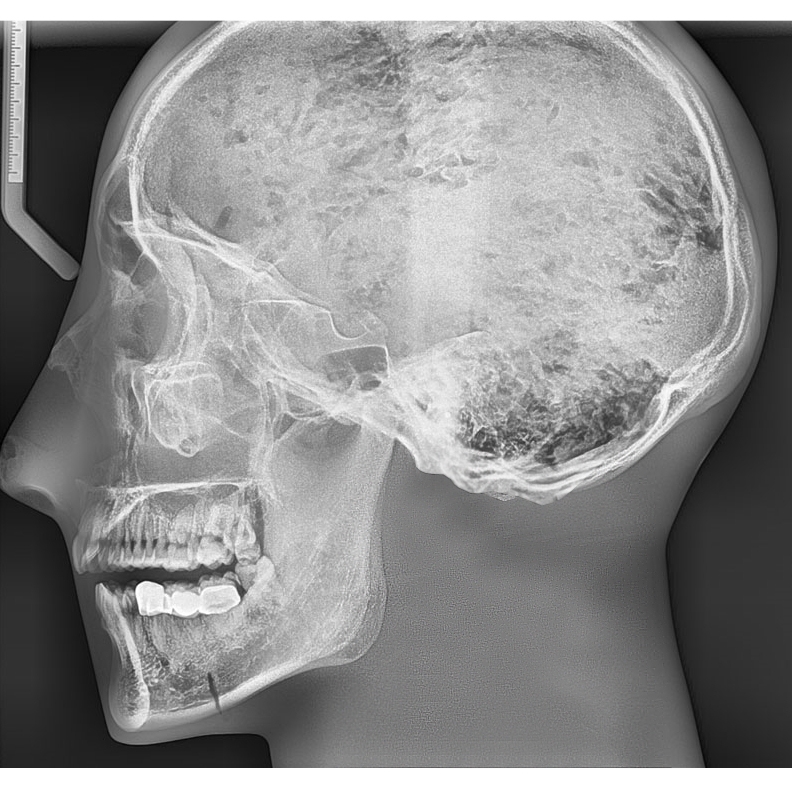

1.模型包含具有天然齿列的真实人类颌骨和5-7截颈椎,整体包埋于软组织等效材料中

2.头骨是医学教学用头骨,没有降解迹象

3.牙齿为未脱落的天然牙齿,部分牙齿有牙科修复痕迹。

4.模式可显示完整的头部骨骼解剖结构,但是没有软组织或软骨解剖,没有气管

头骨与下颌骨及不含颈椎